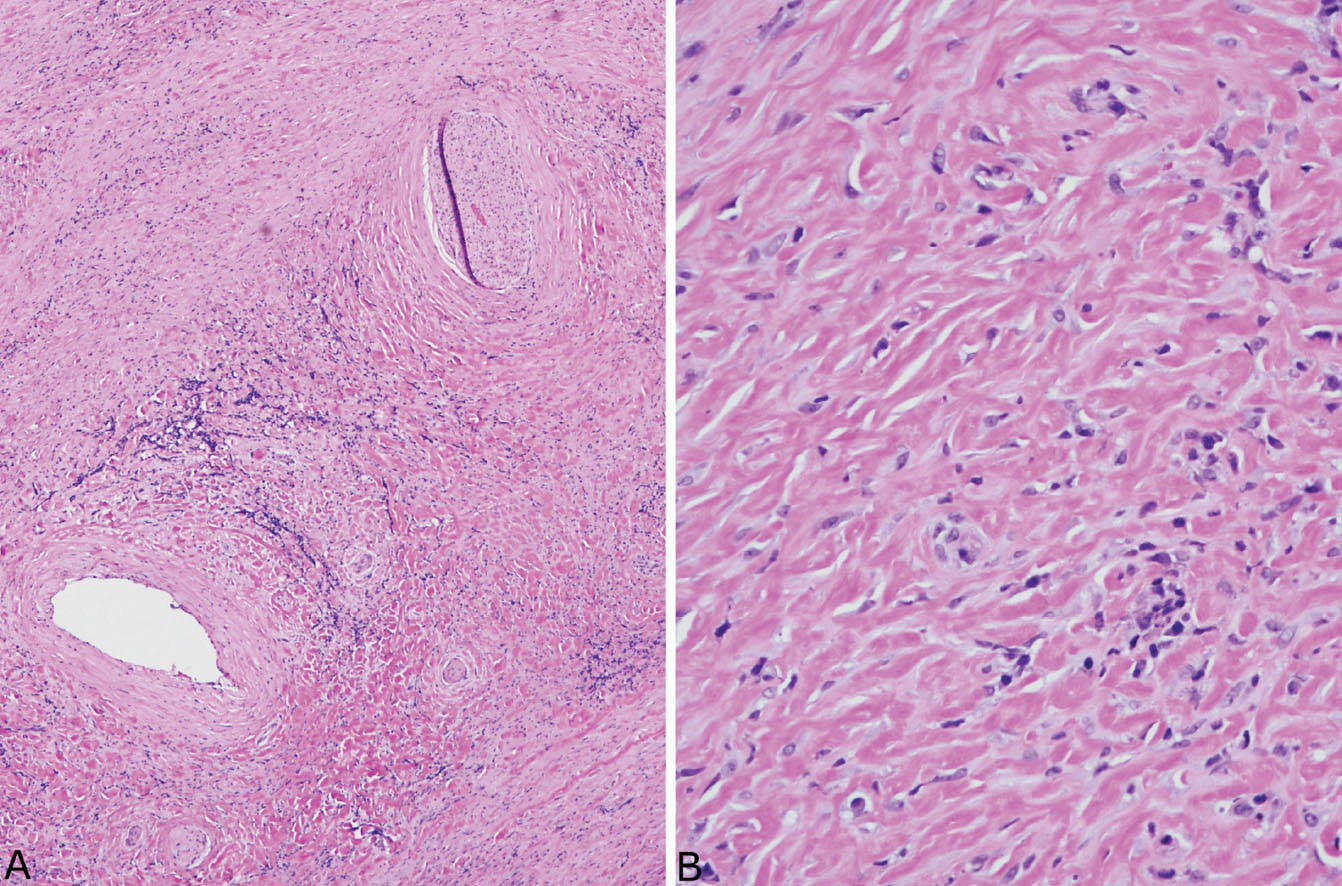

Исследование: микропрепарат молочной железы в медицине

Раздел: Снимки-откровения